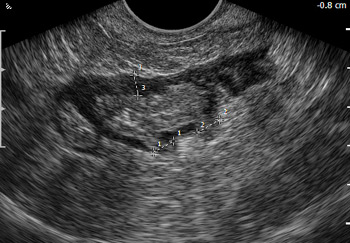

Трансвагинальное 2D ультразвуковое исследование сигмовидной кишки пораженной дивертикулами.